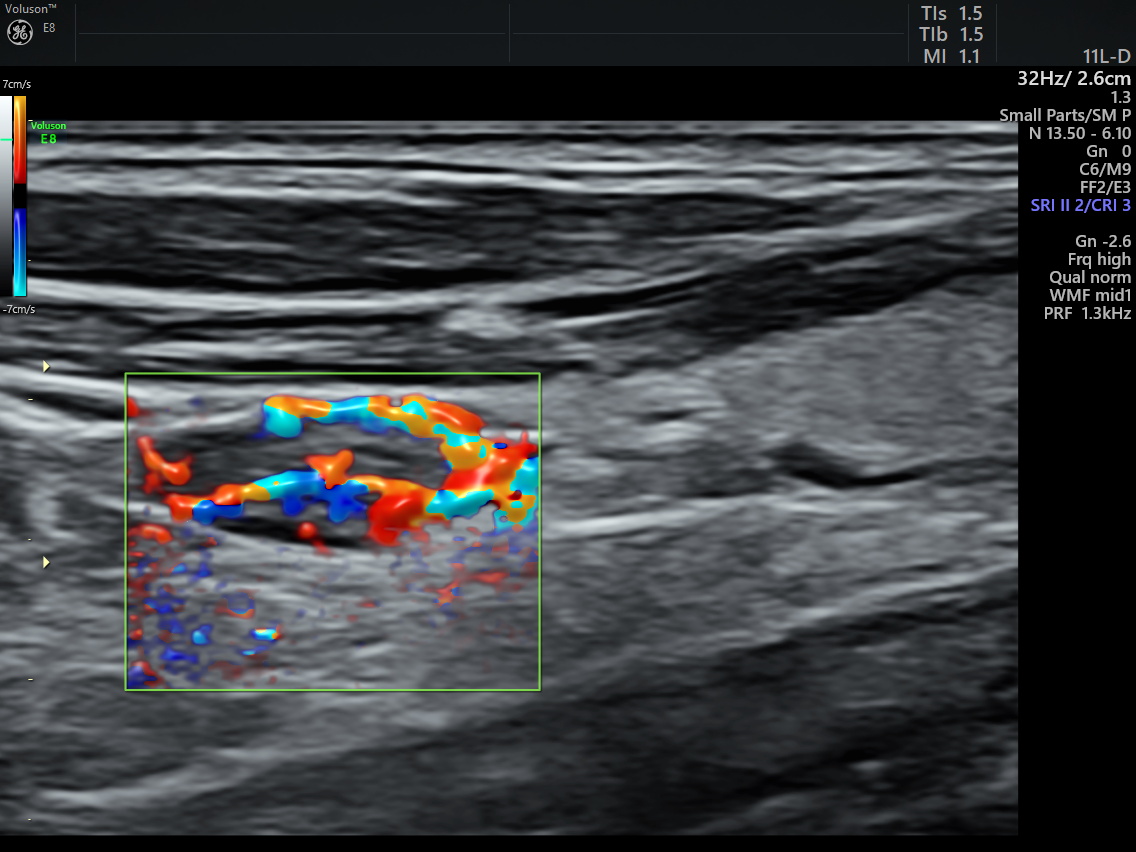

治疗前病灶血流丰富 治疗后病灶血流消失

术中,在高频超声的实时引导下,通过穿刺针水隔离病灶部位与周围组织器官,通过精准导航在完整消融病灶的同时,最大程度避免了对周围正常组织的损伤,仅用时数分钟就完成了整个治疗。术中术后患者未出现声音嘶哑及出血等并发症,术后即刻超声造影显示病灶区无增强,提示消融完全,在住院19小时后患者顺利出院。出院前复查甲状旁腺素12.4pg/ml,呈“断崖”式下降,血钙2.46mmol/L,标志着腺瘤病灶被完全灭活,甲状旁腺功能异常得到纠正,血钙恢复到正常水平,治疗效果显著。